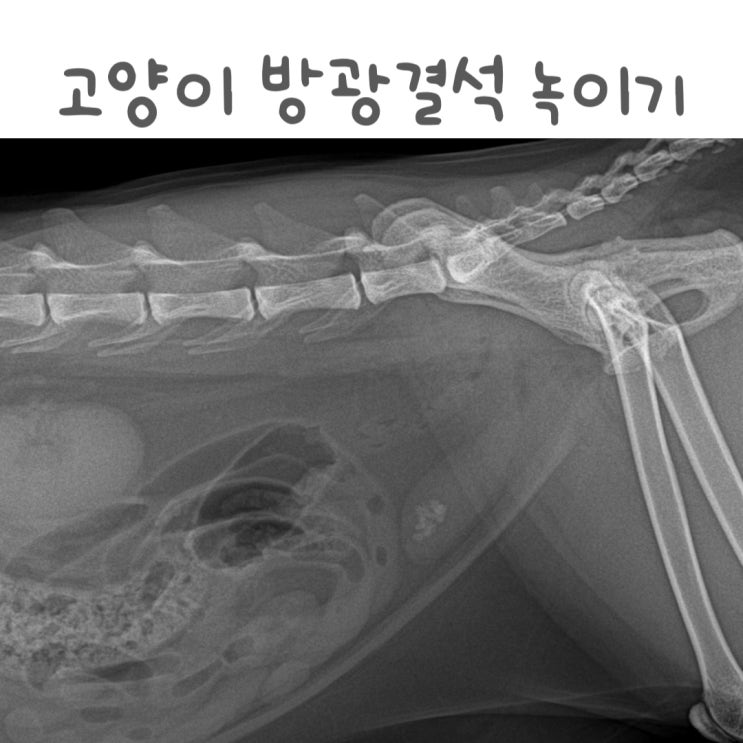

고양이 방광 결석 수술없이 치료하기 ( 처방사료 음수량 시스테이드 )

동이의 방광염 원인은 방광에 있는 결석 때문인데요. 작년 10월 병원 내원 당시의 엑스레이 사진에서도 선...